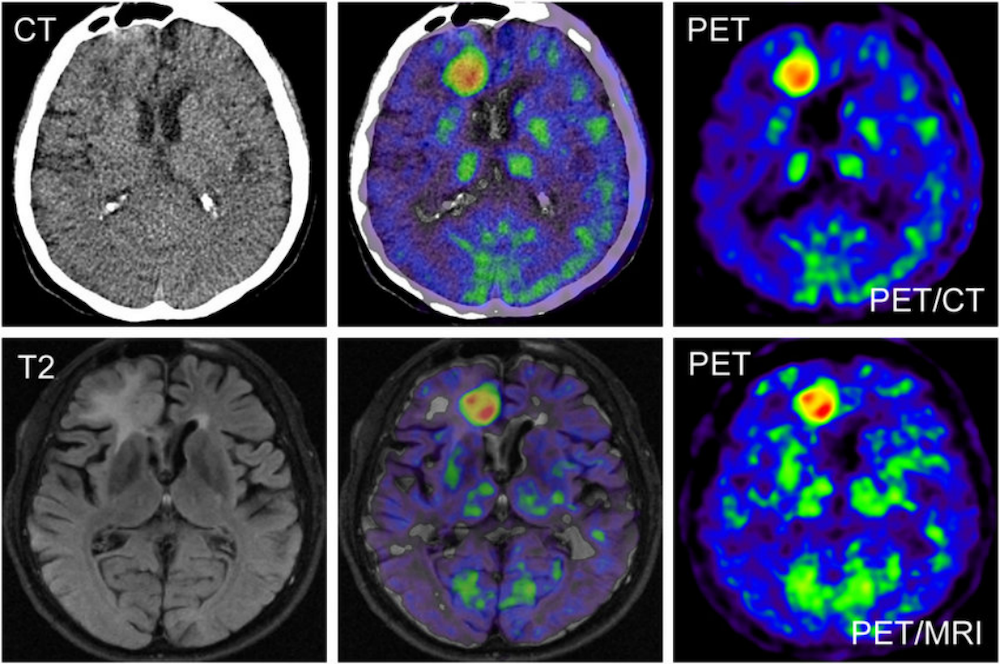

图6:胶质瘤的18F-FDG PET/MRI图像,PET/MRI比PET/CT显示病灶定位更加精确

在信息获取方面,PET/MRI将肿瘤病灶的解剖、分子和功能信息结合起来,有利于提高诊断的敏感度和特异度,并且有较高的空间分辨率。MRI能够获得高分辨的软组织对比度结构图像、扩散加权图像、动态对比度增强图像、功能磁共振图像和其他专用序列以及MR波谱等,与PET提供的定量生理信息相结合,因此,PET/MRI 在病灶定位方面要优于PET/CT。例如,对头颈部、盆腔、乳腺及肝脏病变,基于MRI的高组织对比,PET/MRI的定性、定位更精准。现有的研究数据也显示,PET/MR可用于各种类型的恶性肿瘤,得益于MRI的多参数,PET/MRI能够更好地定位病灶,例如骨转移病灶和前列腺内病灶侵犯程度;而在评估肺部肿瘤时准确率和PET/CT相当。PET/MRI可开发更多肿瘤特异性诊断探针,挖掘和利用MRI的功能性多参数信息,评估其增益价值,将有助于获取更多恶性肿瘤的特征性诊断信息,更灵敏地成像、更准确地定位,高质量地实现肿瘤的早期诊断。